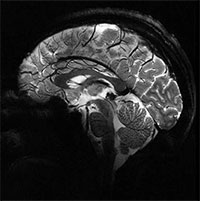

Hình ảnh rõ nét nhất về bộ não chúng ta từ siêu máy quét MRI

Những triển vọng được mở ra bởi cỗ máy độc đáo này trên thế giới là rất lớn, giúp các nhà khoa học thiết lập các chẩn đoán tốt hơn cho nhiều loại bệnh về não.